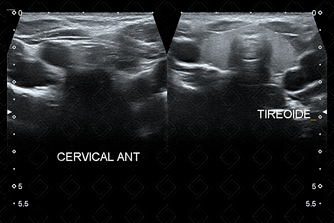

Texto alternativo para a imagem Figura 3. É avaliada, ainda, a glândula tireoide e os espaços cervicais laterais, anteriores e posteriores. Créditos: Dra. Elazir Mota - Rio de Janeiro/RJ